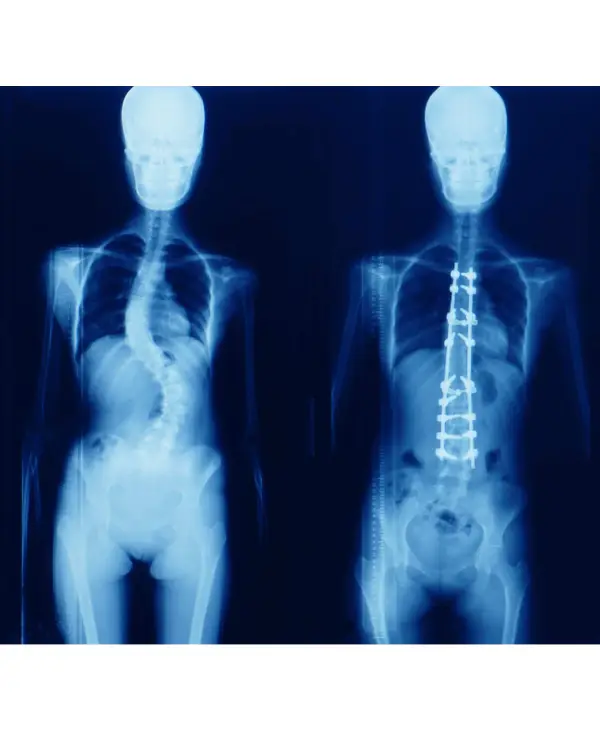

12 year old child with cosmetically and functionally disabling deformity in the back

Diagnosis: Congenital scoliosis with hemivertebra and unsegmented bar

Treatment: Deformity correction with vertebral column resection(VCR) and cage reconstruction

Outcome: child returned to normal life with good self-esteem